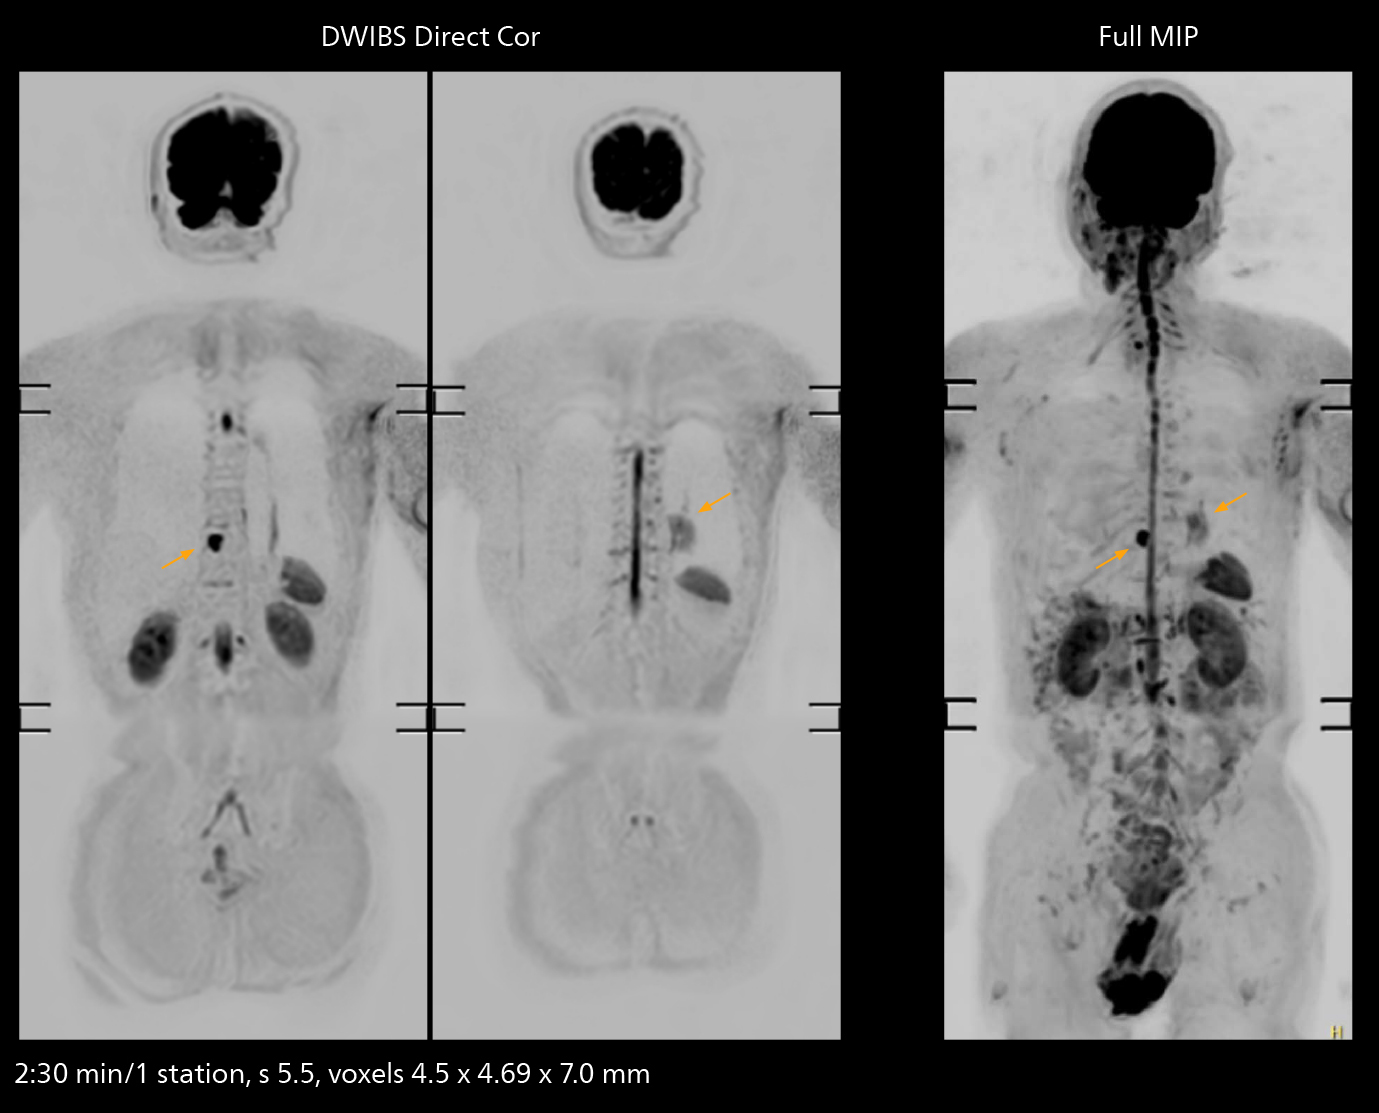

The value of the Elition X gradients is also evident in DWIBS studies. “The fact that we can consistently obtain distortion‐free DWIBS while reducing imaging time at three coronal stations is excellent,” Dr. Makuuchi says. “In these patients, it’s also important that the application of Compressed SENSE to T2‐weighted, STIR and mDIXON sequences has no impact on the examination time of whole‐body imaging. As a result of the increased speed and higher image quality we realize, DWIBS studies have now become routine examinations.”

With SmartPath to Elition X the team can obtain excellent quality DWIBS imaging and reduce imaging time. Other sequences also fit in the examination slot. This case shows left paravertebral neurogenic tumor and Th10 vertebral hemangiomas.